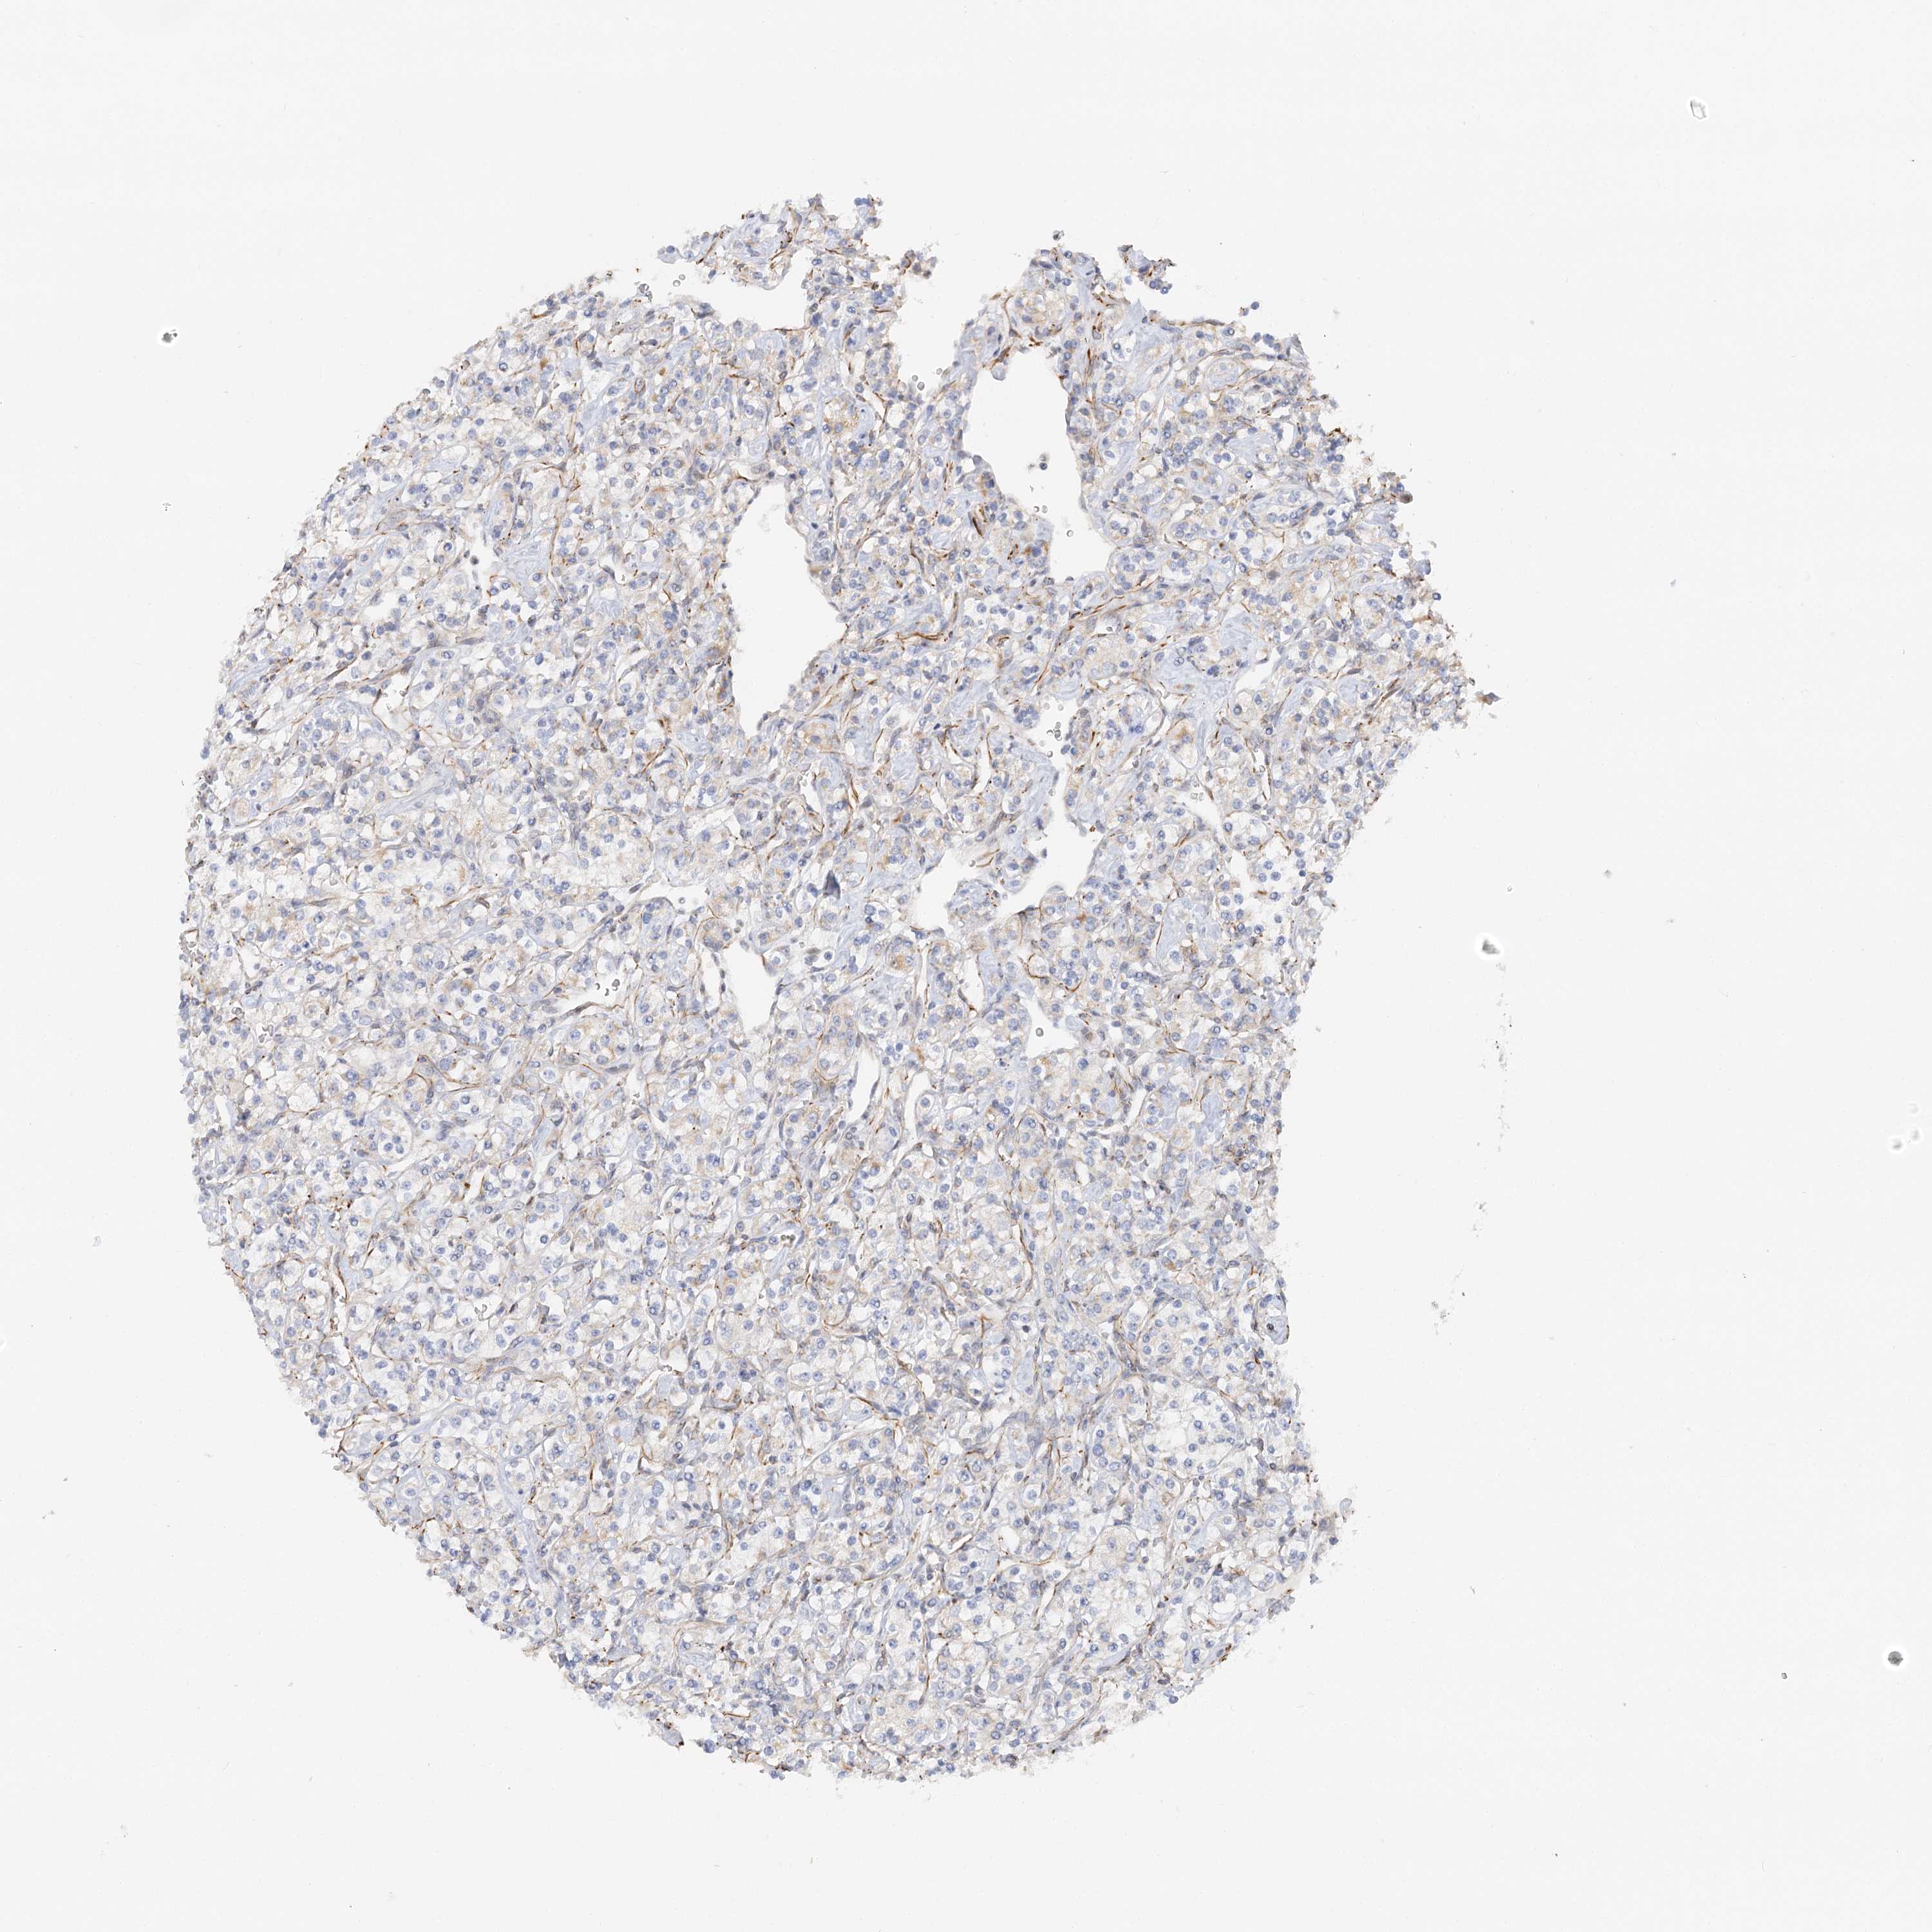

KIDNEY RENAL CLEAR CELL CARCINOMA (TCGA) - Interactive survival scatter ploti

The Survival Scatter plot shows the clinical status (i.e. dead or alive) for all individuals in the patient cohort, based on the same data that underlies the corresponding Kaplan-Meier plots. Patients that are alive at last time for follow-up are shown in blue and patients who have died during the study are shown in red.

The x-axis shows the expression levels (FPKM) of the investigated gene in the tumor tissue at the time of diagnosis. The y-axis shows the follow-up time after diagnosis (years). Both axes are complimented with kernel density curves demonstrating the data density over the axes. The top density plot shows the expression levels (FPKM) distribution among dead (red) and alive patients (blue). The right density plot shows the data density of the survived years of dead patients with high and low expression levels respectively, stratified using the cutoff indicated by the vertical dashed line through the Survival Scatter plot. This cutoff is automatically defined based on the FPKM cutoff that minimizes the p-score. The cutoff can be changed by dragging the vertical line or by entering a cutoff value in the square labeled "Current cut-off".

Under the Survival Scatter plot the p-score landscape (black curve; left axis) is shown together with dead median separation (red curve; right axis). Dead median separation is the difference in median mRNA expression between patients who have died with high and low expression, respectively. It is calculated as follows: median FPKM expression of dead patients with high expression - median FPKM expression of dead patients with low expression. This is intended to aid the user in visually exploring custom cutoffs and the associated p-scores and dead median separation.

Individual patient data is displayed and can be filtered by clicking on one or more of the category buttons on the top of the page. Categories describing expression level and patient information include: high, low, alive, dead, female, male and tumor stages. The scale of the x-axis can be toggled between linear and log-scale by clicking on the "x log" button. Mouse-over function shows TCGA ID, patient information and mRNA expression (FPKM) for each patient.

& Survival analysisi

Kaplan-Meier plots summarize results from analysis of correlation between mRNA expression level and patient survival. Patients were divided based on level of expression into one of the two groups "low" (under cut off) or "high" (over cut off). X-axis shows time for survival (years) and y-axis shows the probability of survival, where 1.0 corresponds to 100 percent.

NELL2 is not prognostic in Kidney Renal Clear Cell Carcinoma (TCGA)

: 0.59

Average pTPM 2.0

Number of samples 521